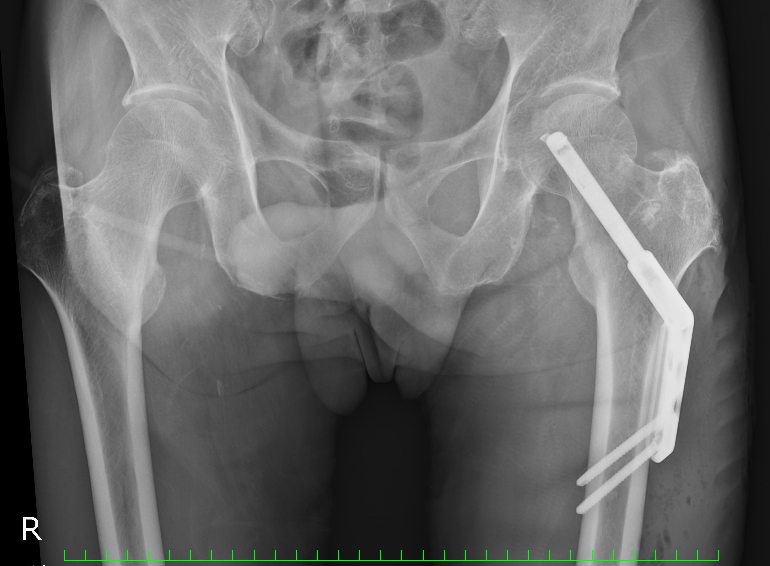

で,以下が手術直後のX線画像。

割とゴツいものが入ってます。 こいつと一生付き合うわけですな。